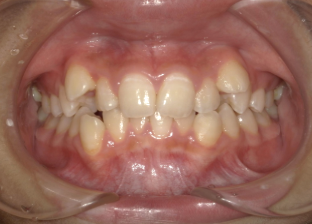

重度叢生・八重歯症例画像

重度(歯が大きく重なっている)の方の場合

歯が深く重なっていて一部の歯がほとんど見えなかったり、八重歯が大きく飛び出しているような、歯列全体のガタつきが強い状態です。かみ合わせも不安定になりやすく、「どこで噛んでいるのか分からない」「磨き残しが多い」と感じる方も少なくありません。 このレベルでは、抜歯によってしっかりスペースを確保したうえで整えていく矯正治療が選ばれることが多く、必要に応じて顎の幅や口元のボリュームなども含めて、トータルでバランスを整える計画を立てます。

治療期間は1年半〜2年ほどとやや長めになりますが、丁寧に進めることで見た目・噛みやすさ・お手入れのしやすさまで総合的に改善が期待できます。